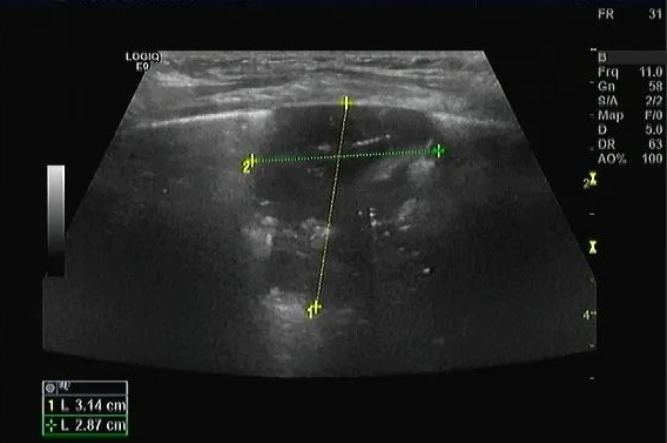

病例三:患兒5歲,咳嗽、發(fā)燒2日,右肺部分實(shí)變,提示肺炎。